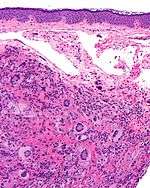

| Micrograph of a juvenile xanthogranuloma with the distinctive Touton giant cells. H&E stain. | |